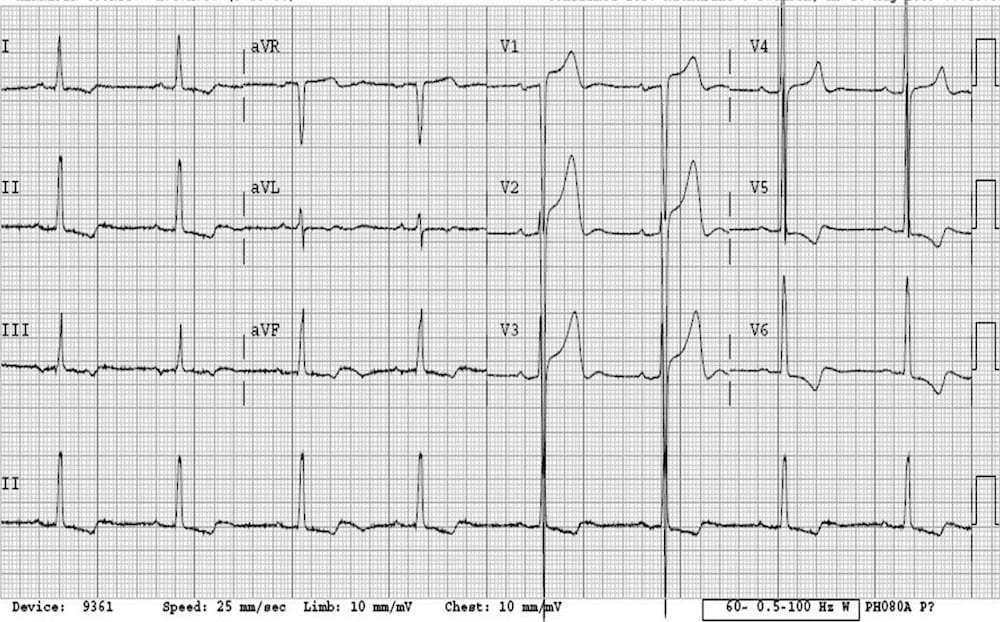

This is an ECG of polymorphic VT (specifically, Torsades de Pointes – a type of polymorphic VT). The varying QRS morphology can be appreciated, with the characteristic morphology of QRS complexes “twisting” around the isoelectric line.

https://litfl.com/torsades-de-pointes-ecg-library/

© Life in the Fast Lane. Licensed under CC BY-NC 4.0